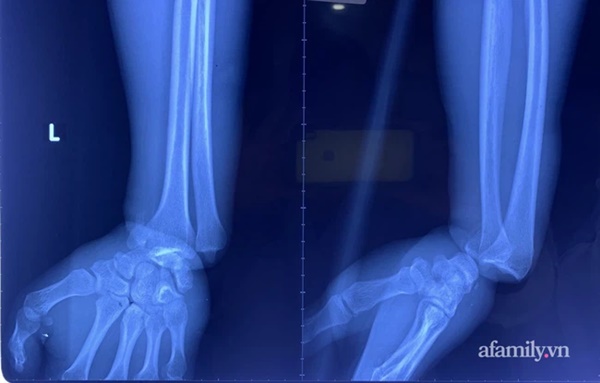

Tại BV Chấn thương chỉnh hình TP.HCM, các bác sĩ thăm khám và chụp X-quang, ghi nhận bệnh nhân có 1 vòng siết chặt ở cổ tay và hết 1 vòng chu vi cổ tay. Dây kẽm siết đã được tháo sau 90 phút gặp nạn.

Bệnh nhân bị gãy trật khớp cổ tay trái.

Hậu phẫu, các bác sĩ chẩn đoán bệnh nhân bị gãy trật khớp cổ tay trái, dập tắc bó mạch thần kinh trụ, dập động mạch quay, dập thần kinh giữa, nhổ dập nát các gân - cơ gân duỗi các ngón...